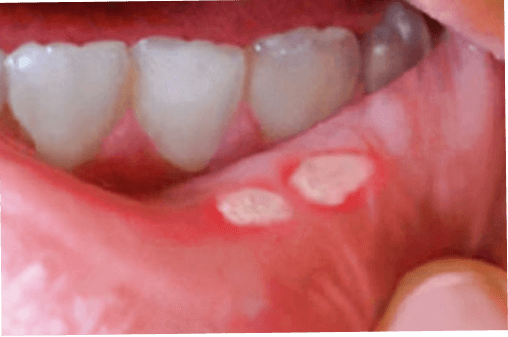

Bilder på afteblåsor

Afteblåsor, även kallade aftös stomatit när flera dyker upp samtidigt, är små smärtsamma sår eller blåsor som uppstår på insidan av munnen, på tungan, insidan av kinderna eller på tandköttet. De är vanliga och helt ofarliga, men de kan vara väldigt besvärande. Afteblåsor är inte smittsamma och brukar försvinna av sig själva inom en till två veckor.

Små, runda eller ovala sår eller blåsor med en vit eller gulaktig yta, samt röd kant.